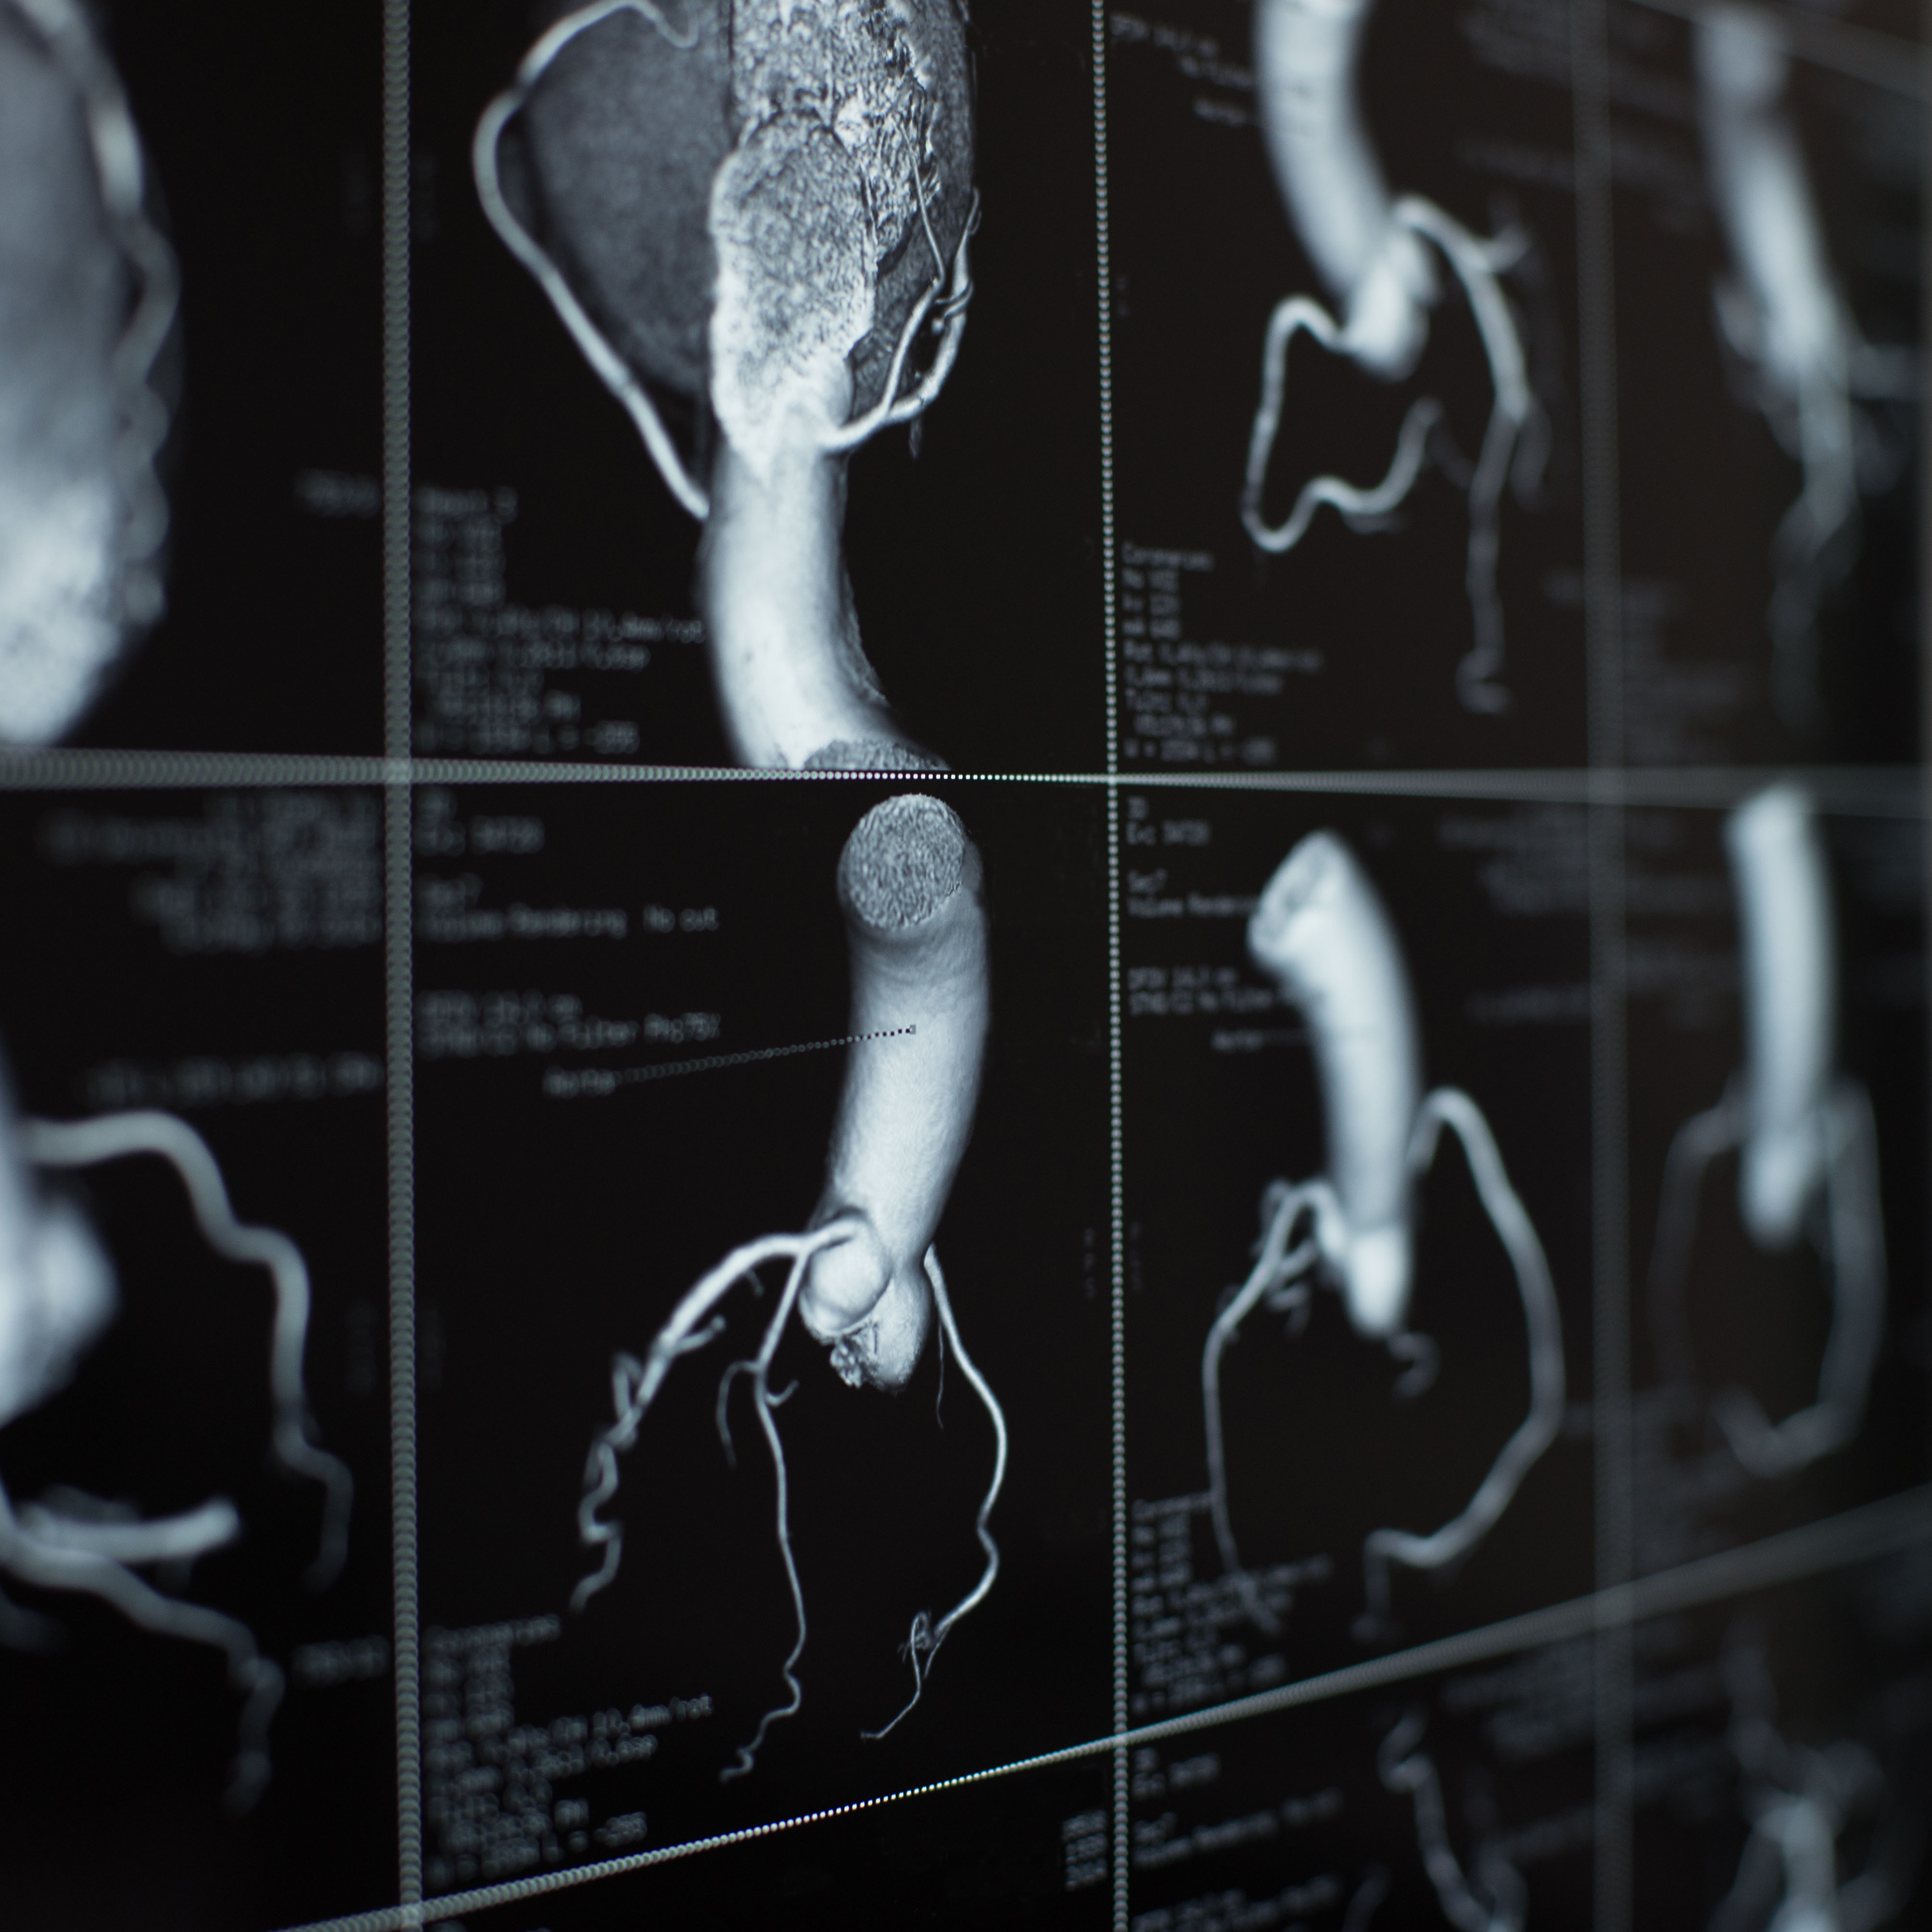

冠状动脉疾病

另一个涉及到心脏血液流动减少的常见问题是冠状动脉疾病(CAD)。这种疾病可引起与HCM类似的症状,包括呼吸短促、疲劳和胸部不适。此外,像HCM一样,它可以发展几十年,几乎没有症状,直到堵塞造成潜在的危及生命的情况,如心脏病发作。冠状动脉疾病通常是通过心脏的CT扫描来诊断的,它可以发现钙沉积和阻塞;同时,此图像可能没有显示HCM所特有的心肌增厚。